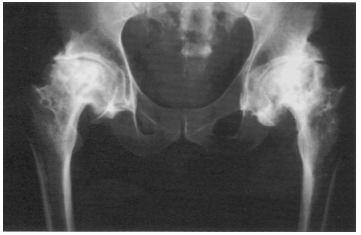

58 48 歲男性於台東海域從事捕抓龍蝦之工作已 25 年, 他從船上以壓縮空氣打入橡皮管作為呼吸管道,一天 在水面下 15 公尺處工作 4~5 小時。就診時雙腿行動 已有困難,須以枴杖或輪椅代步。X 光檢查如圖所示, 則其正確診斷應為下列何者?

(A)無菌性骨壞死 (B)金伯克氏病(Kienböck’s disease) (C)慢性骨髓炎 (D)骨腫瘤